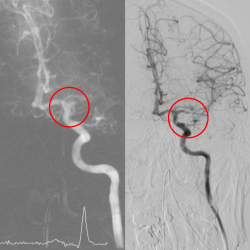

黃金時間搶命|小港醫院取栓團隊成功救治70歲中風婦 | 焦點時報

強化急重症醫療 小港醫院取栓團隊黃 金時間搶救腦中風。〈圖/記者翻攝〉 【焦點時報/記者 蔡宗憲報導】 低溫與早晚溫差大都是腦中風好發的季節,高雄一名70多歲的潘奶奶早上起床時發現左手左腳不會動,左半身無力,說話口齒不清,家人趕緊送往小港醫院急診,經醫院電腦斷層診斷為急...... [閱讀更多]